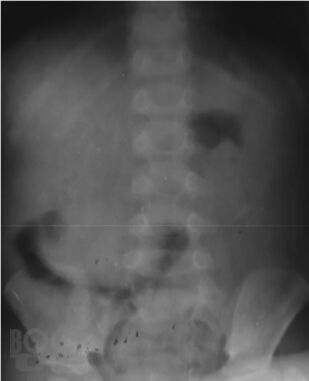

В монографии изложены наиболее актуальные вопросы диагностики и лечения кишечной инвагинации у детей. Представлены данные по истории вопроса, классификация заболевания, диагностический алгоритм. Рассмотрены наиболее частые ошибки в диагностике этого заболевания у детей, подробно обоснован выбор лечебной тактики на основании экспериментального;исследования безопасности консервативного лечения инвагинации кишечника в педиатрической практике. Описаны методики консервативного лечения этого состояния у детей, представлен анализ собственных практических результатов их применения. Отдельно рассмотрены вопросы оперативного лечения инвагинации кишечника у детей, приведено экономическое сопоставление методов лечения этого состояния.